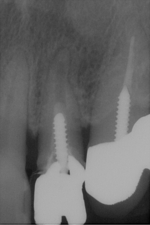

サイナスリフト(骨移植)併用インプラント埋入

ご覧の通り全く骨がないので骨を造りインプラントを埋入しました。

隣の歯も状態が良くなく予後が悪そうです。

抜歯後はインプラントをご希望でしたので、サービスで同部にも骨を移植しておきました。

これで次回オペ時の患者さんの移植のリスクが軽減しました。